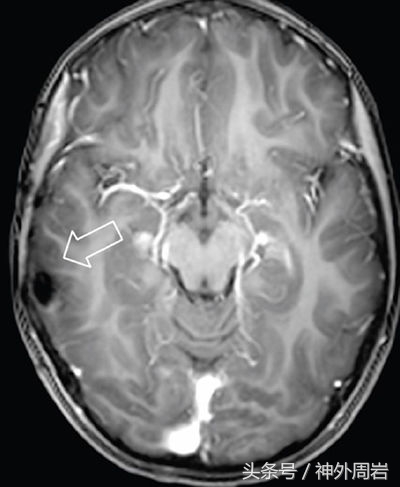

主要发生在5岁以下,除了发笑以外,无情绪变化和意识障碍,几乎不伴有其他癫痫症状,多有下丘脑错构瘤,如进一步压迫下丘脑,患者还可出现性早熟症状。

这类患者对药物治疗反应不好,预后差,早期手术切断错构瘤与周围组织的病理联系可减少或终止发作。

主要发生在5岁以上,常由下丘脑错构瘤以外的病灶致病,多与颞叶或额叶的肿瘤、出血、感染、额角或颞角扩大等有关。多伴有其他癫痫症状或意识障碍,但预后较好。8%的痴笑发作由隐源性病因造成(如脑部结构的微笑异常)。